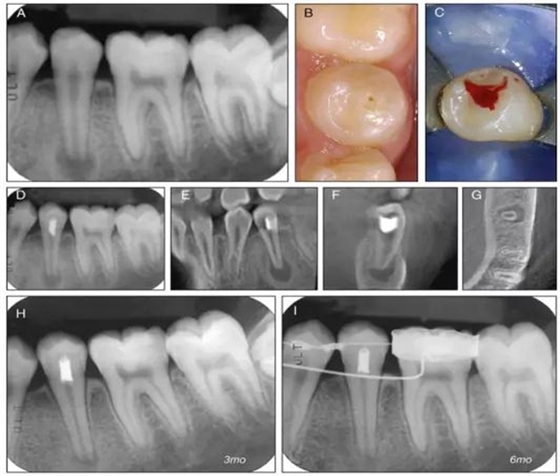

原則上年輕恒牙的牙髓治療應(yīng)盡可能以保存活髓的方式以便不影響牙根繼續(xù)發(fā)育。本文3個病例均描述了根尖尚未發(fā)育完成的下頜前磨牙被確診為牙髓壞死伴有大面積根尖病損,治療過程中在根管內(nèi)發(fā)現(xiàn)了部分活髓,而采用活髓切斷后都取得了很好的療效。